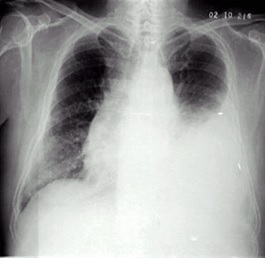

02卷-4.男性,24岁,发热、咳嗽、咳痰4天。诊断(本题满分2.00分)

右上肺炎

A.右上肺不张

B.右上胸膜肥厚

C.右上肺癌

D.右上肺炎

本题答案:D

题目解析:【该题针对“X线-肺炎”知识点进行考核】